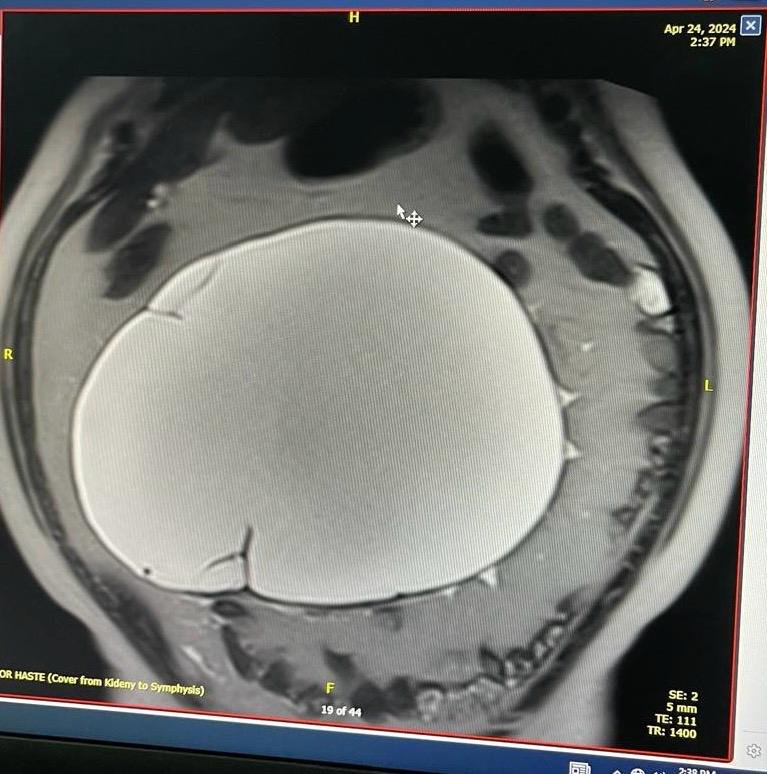

وحضرت المريضة إلى قسم الطوارئ، وبعد الفحص السريري المبدئي قرر الفريق الطبي عمل أشعة موجات فوق الصوتية، أظهرت نتائجها وجود كيس دهني ضخم، الأمر الذي دفع الفريق إلى تحويلها لقسم العيادات الخارجية في المستشفى لإجراء تقييم تفصيلي وفحص أكثر دقة للكتلة، بالإضافة إلى إجراء الرنين المغناطيسي، وبينت الفحوصات الطبية التي أُجريت للمريضة لدى طبيبة النساء والولادة وجود ورم غدي كيسي مخاطي كبير بحجم 10*18*25 سم ما يستدعي إجراء عملية استكشاف واستئصال للورم.

وقد تم نقل المريضة إلى قسم التنويم تمهيدًا لخضوعها للعملية التي تكللت نتائجها بالنجاح ولله الحمد وتم فيها استئصال الورم الضخم خلال مدة لم تتجاوز 30 دقيقة فقط، ووضعها بعد ذلك تحت الملاحظة حتى تماثلت للشفاء بشكل تام وتمكنت من مغادرة المستشفى بالسلامة، مع الأخذ بالاعتبار التأكيد على التزامها في الحضور للمواعيد في العيادات الخارجية، والخضوع للكشوفات الطبية الدورية.